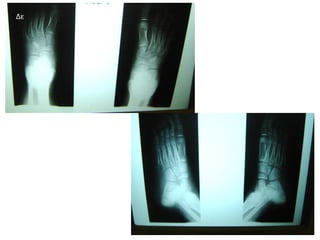

Αγκυλώσεις - Παραμορφώσεις -Διορθωτικές επεμβάσεις

Στόχος: Λειτουργικότητα

Πολυαρθρική μορφή –

Ολιγοαρθρική με χειρουργείο

Αρ Δε

Εξέλιξη βάδισης

Δε

Πορεία βελτίωσης

Πορεία Ν.Ι.Α

Ανισοσκελία με προσαρμογή λεκάνης και κορμού και

εξισορρόπηση, συνεχίζει να φορά πάτους για την

βλαισότητα.

1 μήνα μετά – ανισοσκελία με προσαρμογή λεκάνης και ΣΣ και σύστοιχης

Αρ ΠΔΚ σε θέση βλαισότητας αντιρροπιστικά

Ανισοσκελία 8 χιλιοστά 8 μήνες μετά

Ανισοσκελία 5 χιλιοστά

12os 2013

Αποτελέσματα υπερήχου (US)

25/10/13 Παρουσία υγρού Αρ ΠΔΚ - Εετρ

24/1/2014 Σχεδόν επάλειψη της

συλλογής υγρού Αρ ΠΔΚ

Παρουσία υγρού στην οπίσθια

Αστραγαλοκνημιαία άρθρωση

MRI 11/2013 οστεχόνδρινες βλάβες

πτέρνας και υγρό στην

αστραγαλοπτερνικής άρθρωσης

5/2012 πάχυνση αρθρικού υμένα